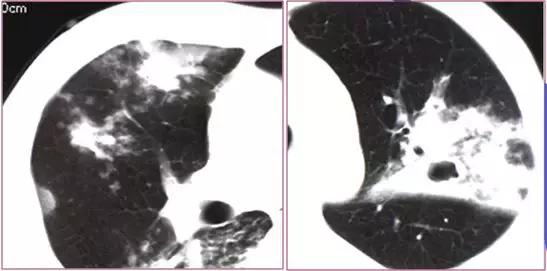

CT征象一:树芽征

由终末细支气管和肺泡腔内病变形成的小结节影与分支细线影构成的酷似春天的树枝发芽状,称“树芽征”(tree-in-bud)

CT表现:多在肺外围支气管末梢呈2-4mm大小结节与树枝状的高密度影。

意义:多表明有小气道病变如:细支气管炎症、弥漫泛发性细支气管炎及肺结核病灶或播散等

末梢细支气管扩张形成粘液栓——酷似“树芽征”

末梢细支气管与肺泡结核灶及播散——酷似“树芽征”

“树芽征”:活动性肺结核支气管播散;泛细支气管炎